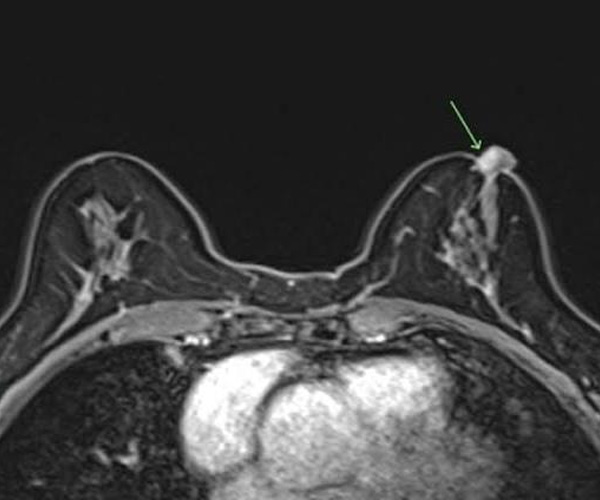

Nipple Adenoma & Other Diseases